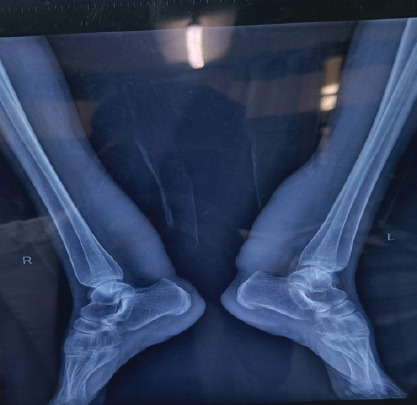

Case report: We hereby present a rare case of a 33-year-old female with bilateral tendoachilles xanthoma who presented with complaints of swelling and pain in the bilateral lower leg region treated with surgical debulking. Monthly follow-up suggested fair healing, pain reduction, and maintained Achilles tendon function.